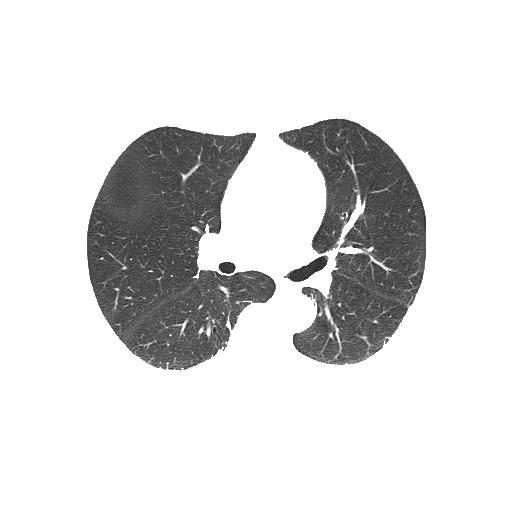

The problem is the segmented lung still contains white borderers like this:

Segmented lung (output):

segmented lung

Unsegmented lung (input):

unsegmented lung